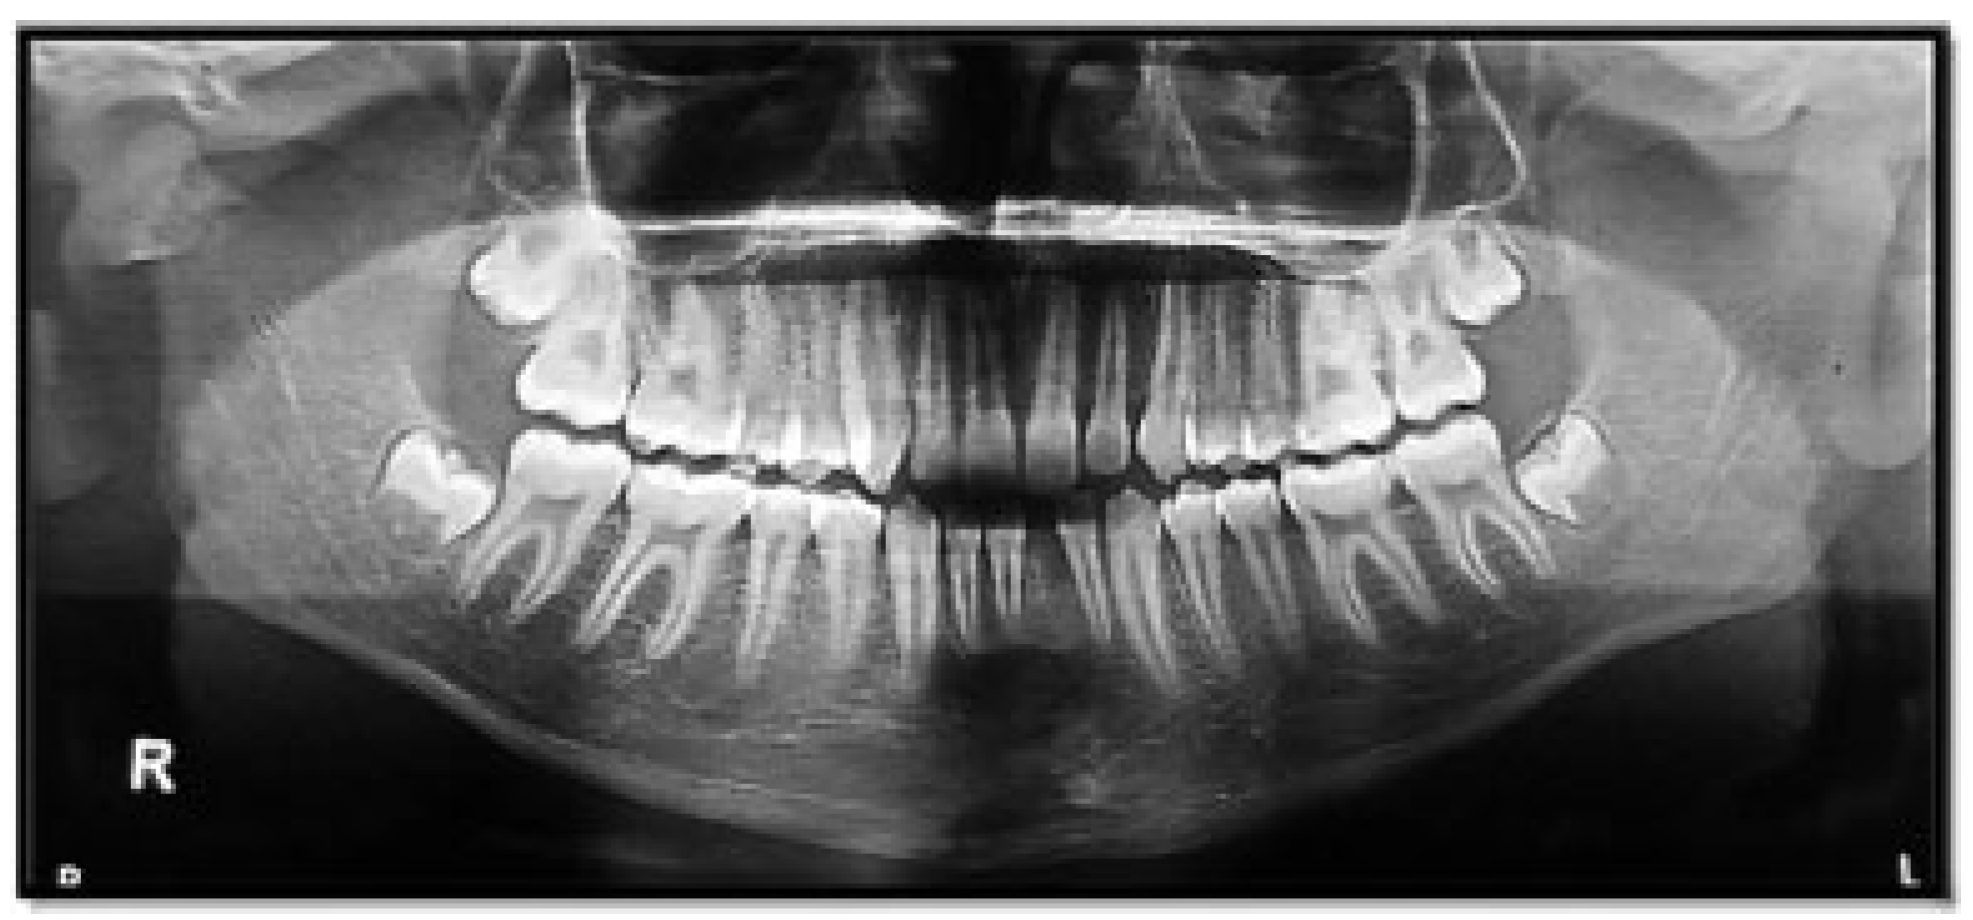

Figure 7. Right subcondylar fracture with the absence of mandibular third molar.

Of the condyle fractures, 76 patients (58.46%) had absence of mandibular third molars, whereas 54 patients (41.54%) had third molars. The absence of a mandibular third molar in condylar fractures was statistically and significantly higher than in patients where third molars were present (Figure 5, Figure 6, Figure 7 and Figure 8; Table 4).

Of the 54 mandibular condyle fracture patients, who had a lower third molar, the highest incidence was seen in vertical angulation (34 patients; 62.96%) followed by mesioangular angulation (13 patients; 24.07%), distoangular angulation (5 patients; 9.26%), and horizontal angulation (2 patients; 3.70% [Figure 9, Figure 10 and Figure 11; Table 5]), respectively.